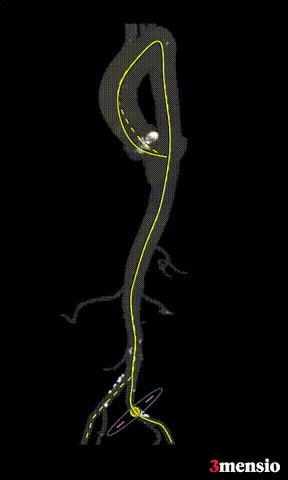

外周血管及主动脉弓解剖:

③患者近横位心,术中应加以snare辅助输送器过弓。